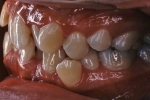

(左:治療前、右:治療後)

第4症例 Class Ⅱ divison 2 (overbite 5mm以上)

しかし、出題基準にも書いてあるように、このケースは欧米の白人によく見られるケースで、東洋人にはきわめて稀である。そこで類似ケースとして過蓋咬合(かがいこうごう)のケースを代替えとして認めるという配慮をしている。過蓋咬合とは非常に強く深く咬んでいる状態を言う。Overbiteとは前歯の垂直的な重なり具合を示す数値で、5mm以上だと上の前歯が下の前歯をほとんど覆い尽くしている感じになるので、前から見ると下の前歯はほとんど見えない状態になる。こういう状態が典型的な過蓋咬合である。典型的なclassⅡ,division 2のケースは過蓋咬合を合併している。